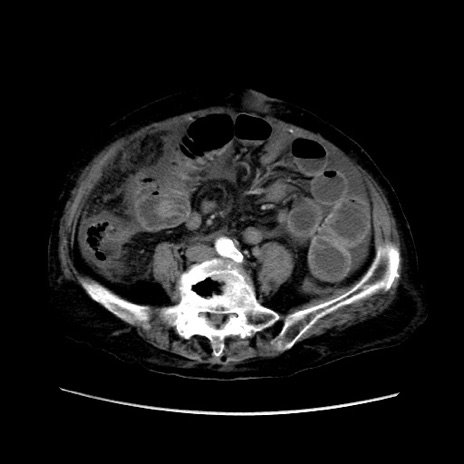

症例31(横断像)

【症例】80歳代 女性

【主訴】腹部膨満感

【現病歴】他院にて肝硬変にてフォロー中。1週間前から便秘、腹部膨満感、臍部腫瘤あり受診となる。

【既往歴】肝硬変

【身体所見】腹部膨隆あり、皮膚変化なし、疼痛なし。

【データ】WBC 4600、CRP 0.25